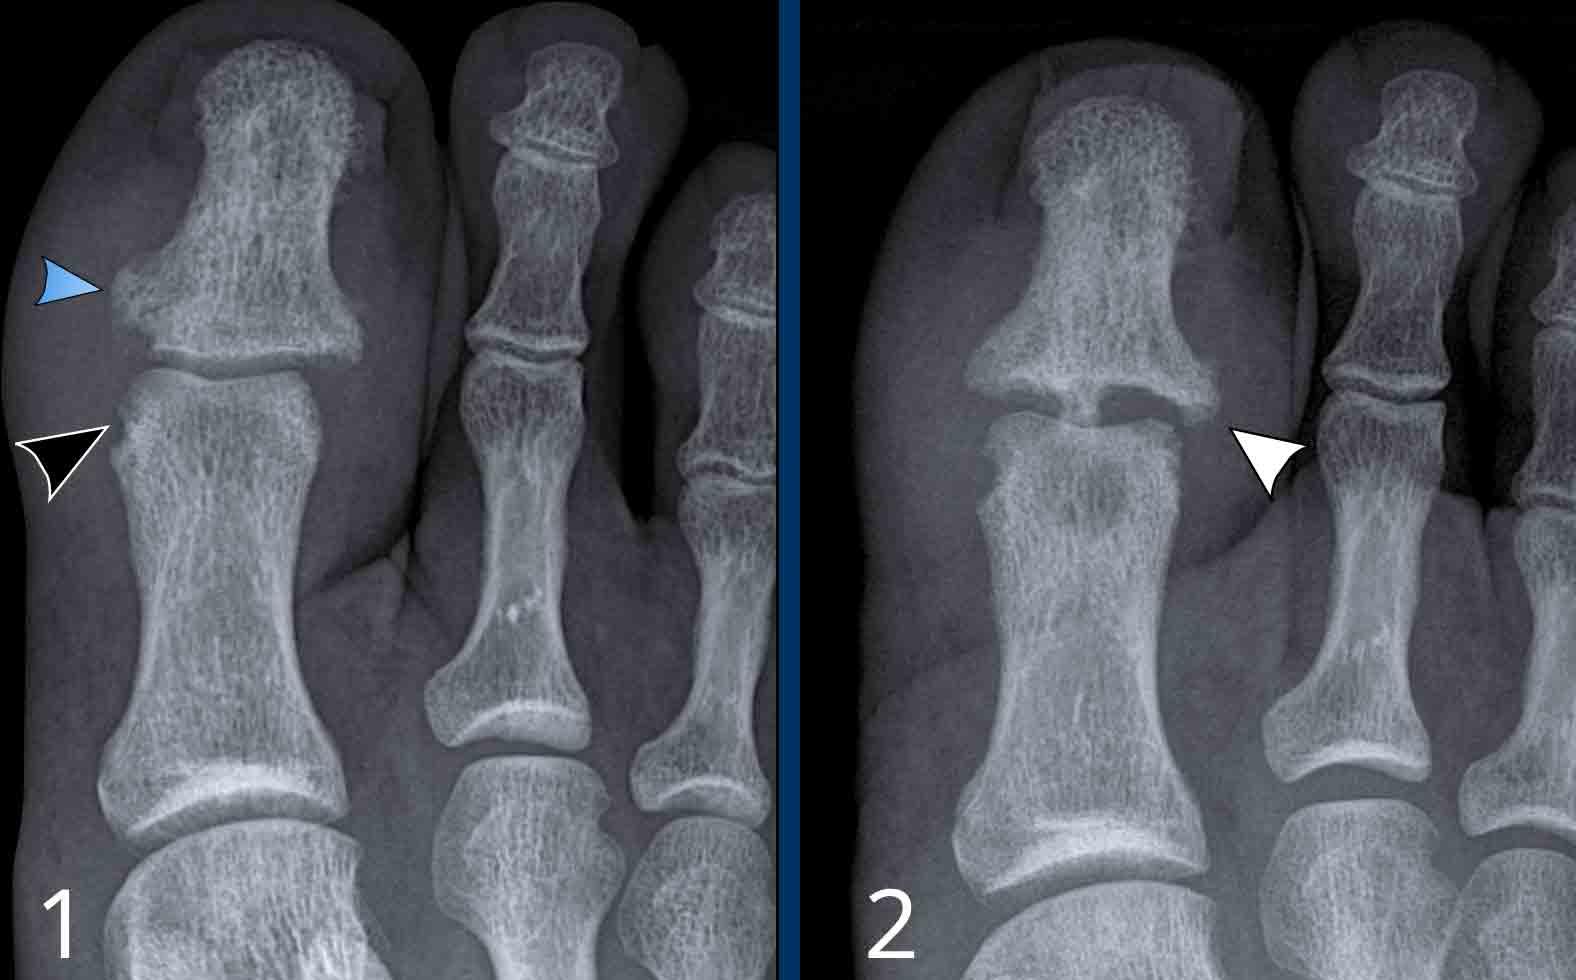

Viêm khớp vảy nến tiến triển

- Hình bên trái cho thấy bào mòn xương ở rìa khớp (mũi tên đen) và hình thành xương mờ nhạt (mũi tên xanh) tại khớp liên đốt ngón (IP).

- Về sau, bệnh tiến triển thành biến dạng bút chì trong cốc điển hình.

Phân bố tổn thương và sự hình thành xương khiến chẩn đoán viêm khớp dạng thấp ít có khả năng.

Các bào mòn xương ở rìa khớp và sự vắng mặt của tổn thương khớp liên đốt xa (DIP) ở các khớp khác khiến chẩn đoán viêm xương khớp bào mòn ít có khả năng, mặc dù biến dạng bút chì trong cốc có thể trông giống biến dạng cánh hải âu trong viêm xương khớp bào mòn.

A. Biến dạng bút chì trong cốc tại ngón chân thứ 1 và thứ 5.

B. Tiêu xương đầu ngón (acro-osteolysis) với tiêu xương chỏm đốt ngón xa của ngón 2-4 và 5.

Có bào mòn xương tại khớp bàn ngón chân (MTP) 2 và 3.